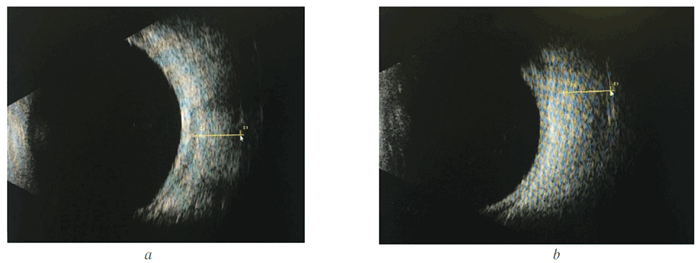

Эхография орбит: нижняя и внутренняя прямая мышцы резко увеличены в размерах (рис. 2).

Через 4 месяца после начала лечения острота зрения восстановилась до 1,0 с коррекцией, ВГД остаётся компенсированным (18 мм рт. ст.) без медикаментозной коррекции, остаточный экзофтальм — 5 мм (рис. 5). При контрольной эхографии орбит нижняя и внутренняя прямая мышцы уменьшены в объёме, в поперечнике — практически на 1 мм (рис. 6).

Рис. 2. Эхограммы орбит того же больного: а — нижняя прямая мышца, 6,5 мм; Ь — внутренняя прямая мышца, 6,2 мм

Fig. 2. Echograms of patient's orbits: a — lower rectus, 6.5 mm; b — internal rectus, 6.2 mm

Рис. 2. Эхограммы орбит того же больного: a — нижняя прямая мышца, 6,5 мм; b — внутренняя прямая мышца, 6,2 мм

Fig. 2. Echograms of patient’s orbits: a — lower rectus, 6.5 mm; b — internal rectus, 6.2 mm

Через 4 месяца после начала лечения острота зрения восстановилась до 1,0 с коррекцией, ВГД остаётся компенсированным (18 мм рт. ст.) без медикаментозной коррекции, остаточный экзо фтальм — 5 мм (рис. 5). При контрольной эхографии орбит нижняя и внутренняя прямая мышцы уменьшены в объёме, в поперечнике — практически на 1 мм (рис. 6).

Рис. 6. Эхограммы орбиты (по окончании лечения): a — нижняя прямая мышца, 5,6 мм; b — внутренняя прямая мышца, 5,46 мм

Fig. 6. Echograms of orbits after treatment: a — lower rectus, 5.6 mm; b — internal rectus, 5.46 mm